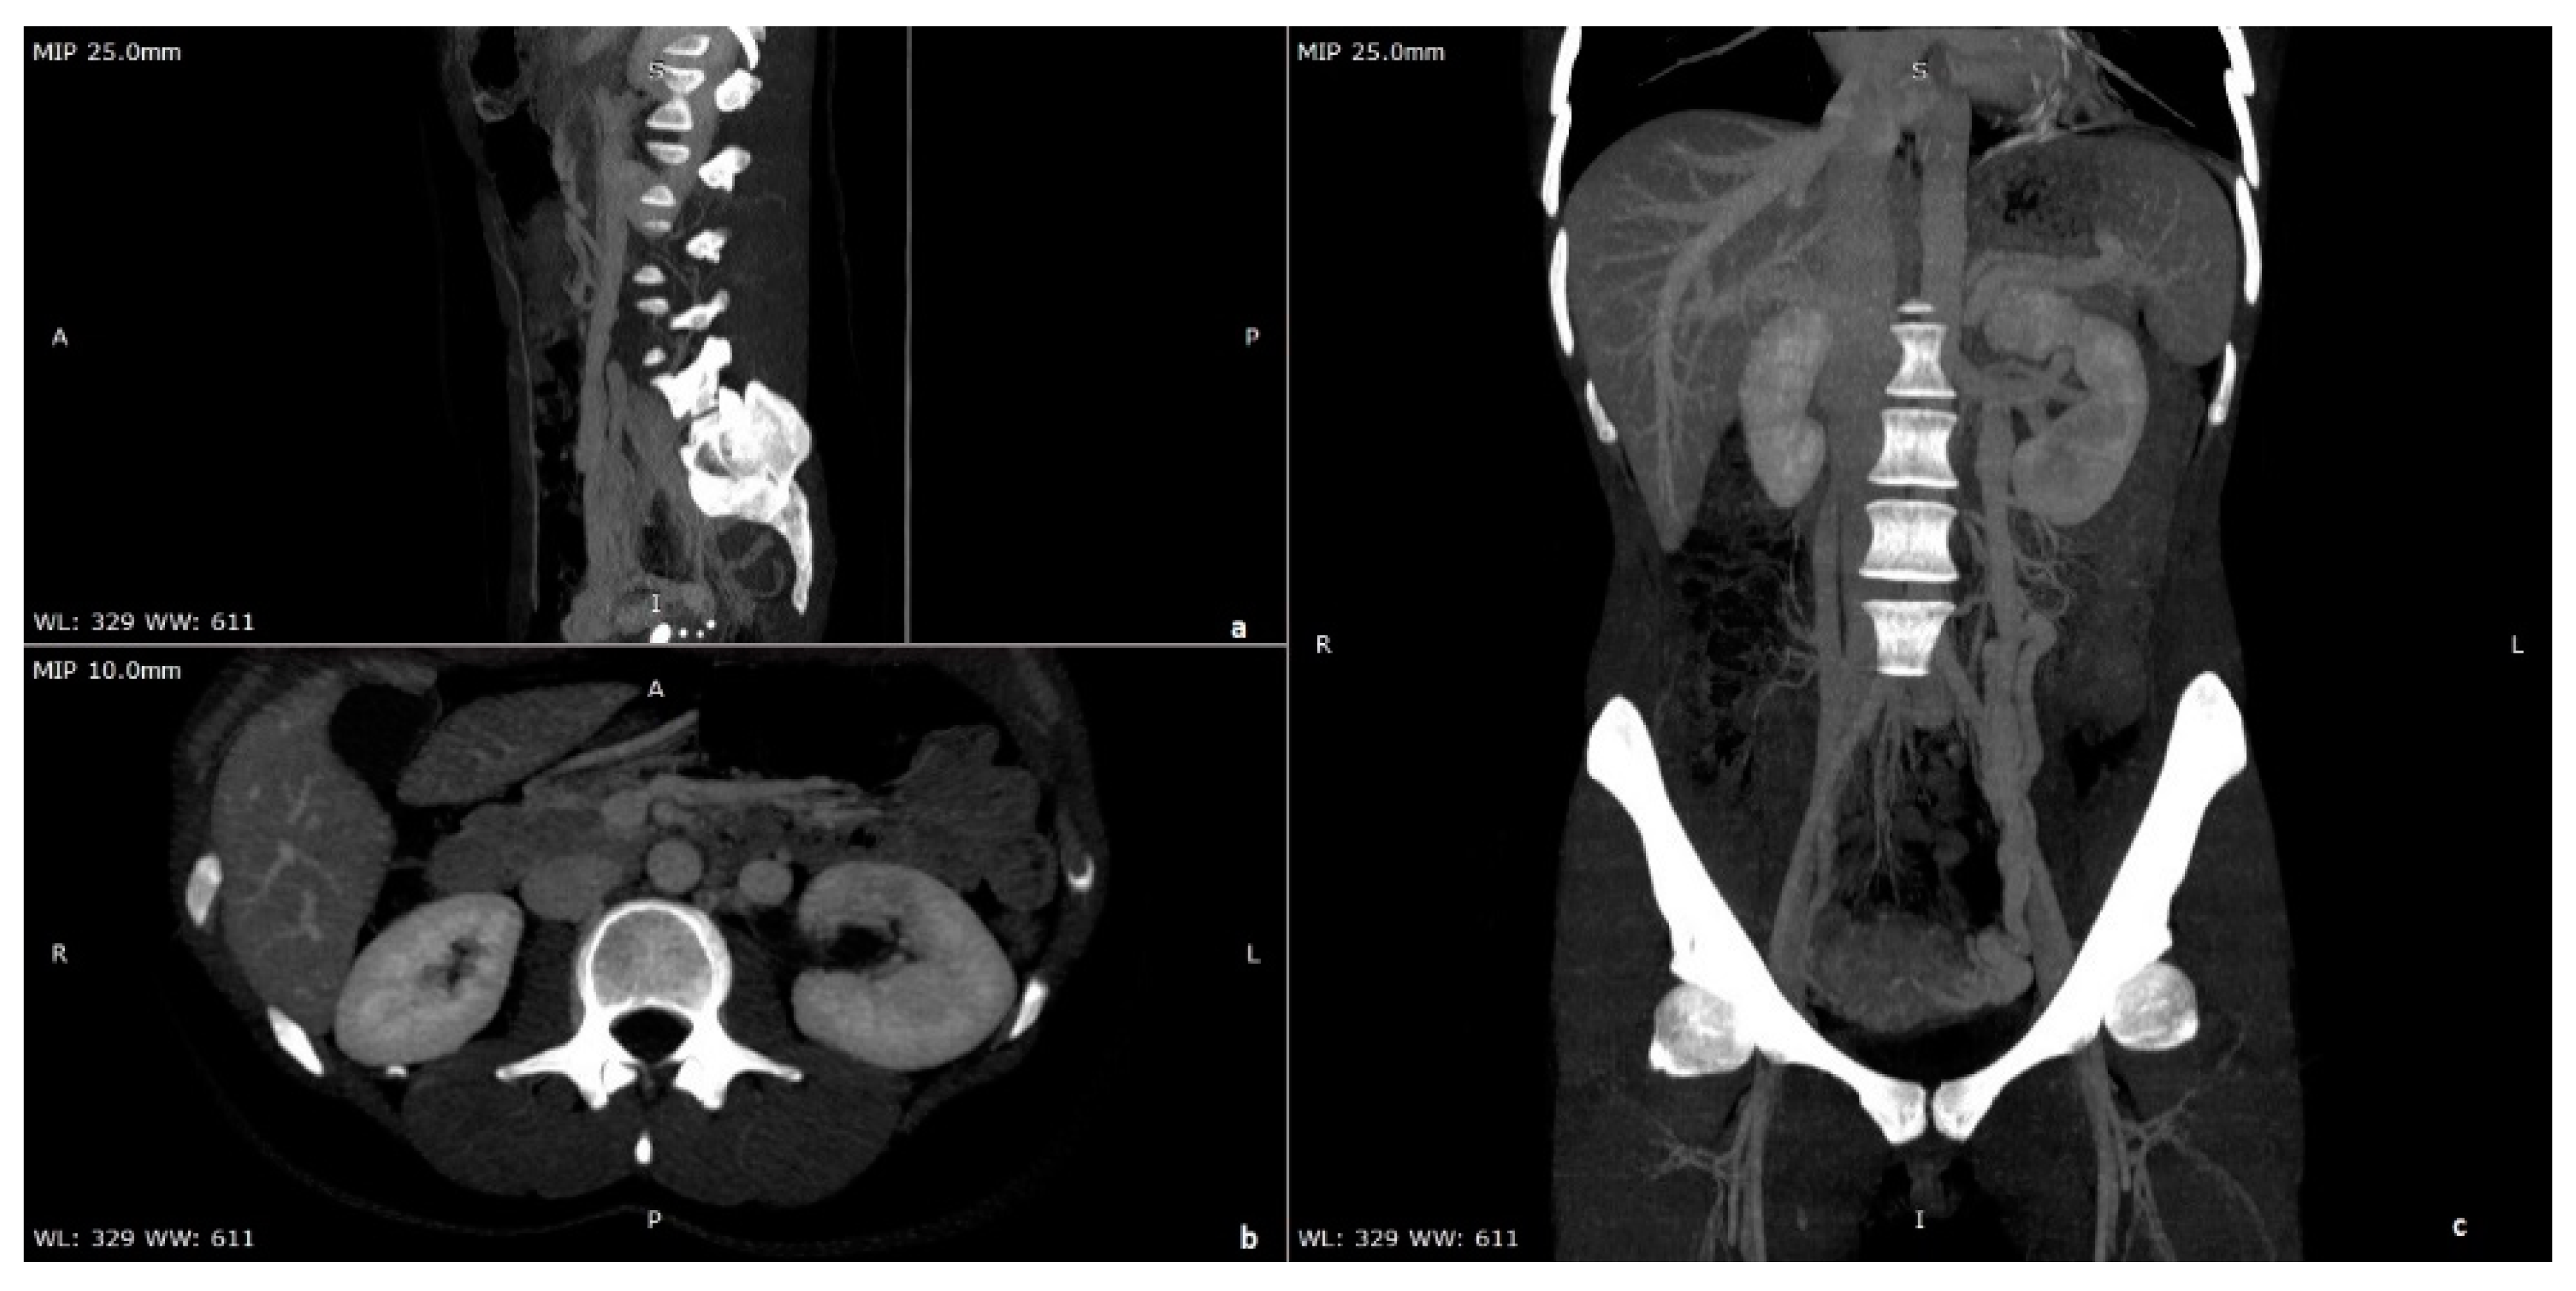

Nutcracker. (a) Left renal vein underneath SMA anterior Nutcracker Nutcracker Syndrome In Females    women with nutcracker syndrome may exhibit symptoms secondary to dilated and incompetent ovarian and uterine veins, including.   nutcracker syndrome (ncs) is an extrinsic compression of the left renal.   nutcracker syndrome (ns) is a condition in which two arteries compress the left renal vein (lrv), interfering with blood flow out of the.   in nutcracker syndrome, symptoms are. Nutcracker Syndrome In Females.